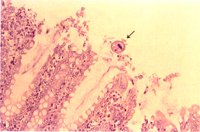

2.大腸:纖維素性壞死性腸炎,粘膜面瀰漫性壞死,腺窩及杯狀細胞增生及炎症細胞蓄積。腸道粘膜表面附有大腸纖毛蟲(Balantidium coli)(圖2)腸腔內有游離的蟲體,高倍可見蟲體前半部細長不對稱的食道及蟲體後部之腸與生殖腺為鞭蟲( Trichuris suis)蟲體的特徵(圖3)